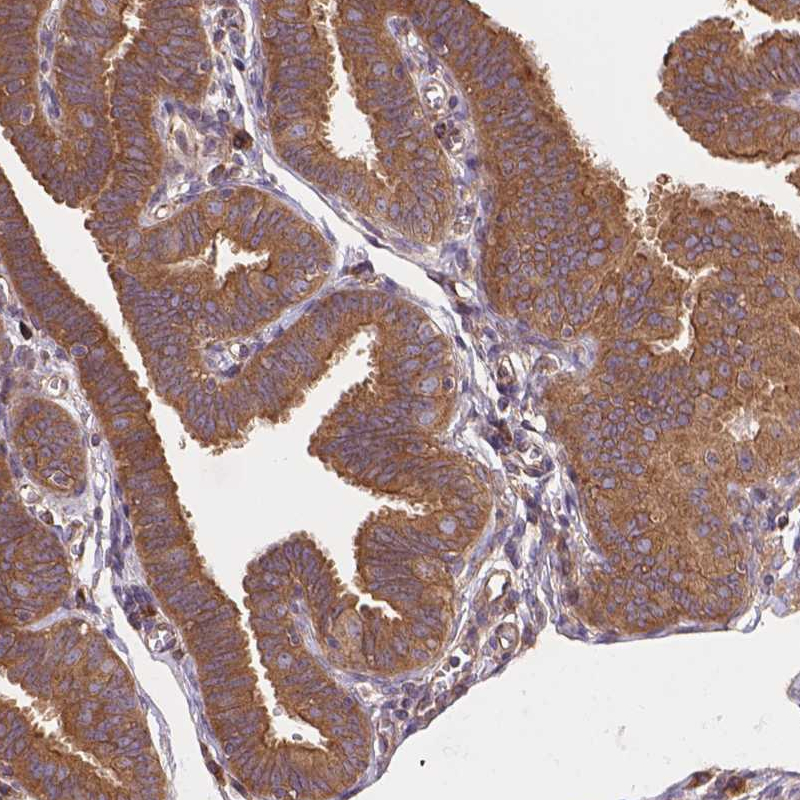

Immunohistochemical staining of human tonsil shows strong cytoplasmic and memranous positivity in germinal center cells.